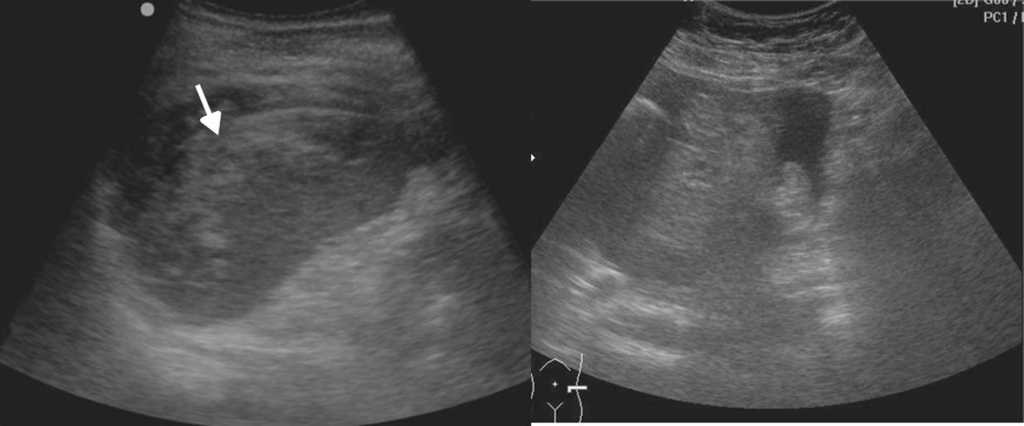

Evaluaci??n musculoesquel??tica

La ecograf??a es el m??todo ideal para la exploraci??n del sistema musculoesquel??tico, en tanto brinda la posibilidad de evaluarlo en reposo o en movimiento, observando los cambios en tiempo real. Adem??s, permite la comparaci??n del sitio exacto del dolor con su lado contralateral, adquiriendo im??genes en panor??mica19.

Los actuales transductores de alta frecuencia (12-18 MHz) tienen excelente resoluci??n para analizar las estructuras superficiales (m??sculos, tendones, ligamentos y bursas) y sus patolog??as20 (figs. 14 y 15). La ecograf??a en escala de grises permite una gran imagen anat??mica de la lesi??n, mientras que el Doppler color identifica la vascularizaci??n del tejido y las im??genes panor??micas otorgan una visualizaci??n extensa del campo de visi??n, que muestra la lesi??n y su relaci??n con las estructuras vecinas (fig. 16).

A pesar de estas grandes ventajas, muchos profesionales elijen otras modalidades diagn??sticas por m??ltiples razones21. Al respecto, vale subrayar que es necesario un profundo conocimiento de la anatom??a de la zona a explorar y su cl??nica para obtener los mejores resultados.